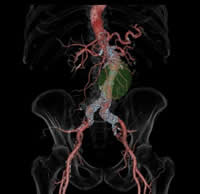

検査は、ベッドに寝ているだけで終了します。また、当院検査は、一回の撮影で同時に複数の輪切り像が得られる最新型ボリュームCTスキャナです。 得られた輪切り画像から下のような精密な立体像を作ることも可能です。

体幹部3次元画像